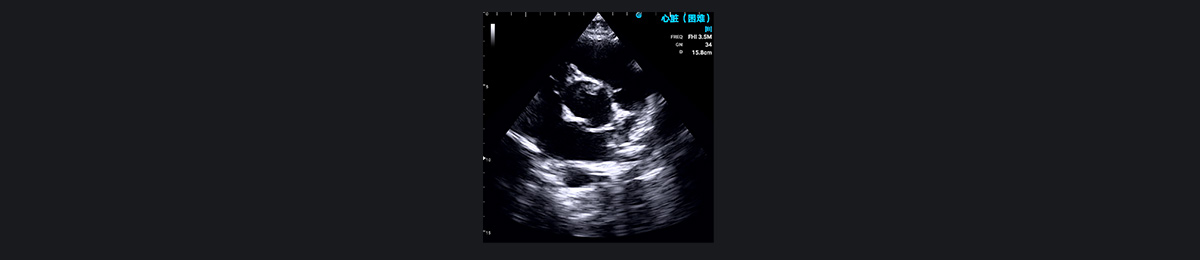

ÔÎØÊµÄÔÒò°üÀ¨ÏÈÌìÐÔÐÄÔಡ¡¢·ÊºñÐÔ¹£×èÐÔÐ¡¡¢Ðļⲿ·ÊºñÐÔÐ¡¡¢·¨ÂåËÄÁªÖ¢¡¢ÍêÈ«ÐÔÐÄÄÚĤµæÈ±Ëð¡¢µ¥ÐÄÊÒ¡¢´ó¶¯Âöתλ¡¢¹Ú×´¶¯ÂöÒì³£ºÍ¶þҶʽÖ÷¶¯Âö°êµÈ¡£³ÉΪÔÒò¡£ SonoEye ÊÖ³Öʽ³¬Éù¼ì²é¿ÉÒÔ¼°Ê±½øÐÐÁÙ´²Õï¶Ï£¬ÒÔÈ·¶¨ÔÎØÊµÄÔÒò¡£

¶þҶʽÖ÷¶¯Âö°ê